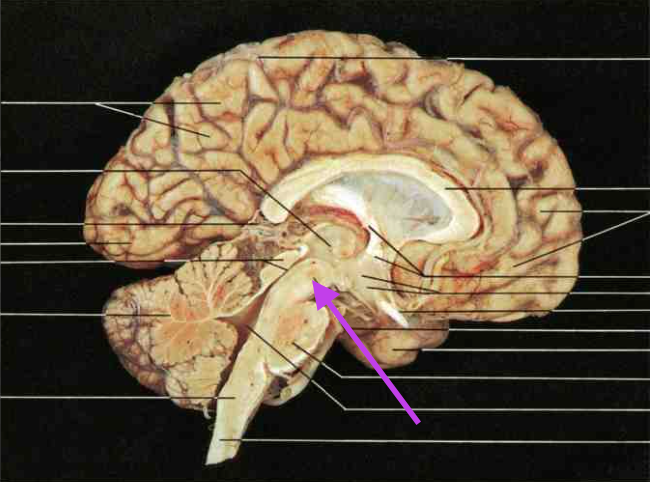

Midbrain. Section is Brain Stem.

Cerebral Aqueduct. Part of Midbrain. Section is brain stem.

Inferior Colliculus. Part of the midbrain. Section is brain stem.

Superior colliculus. Part of midbrain. section is brain stem.

Pons. Section is brain stem.

Medulla oblongata. Section is brain stem.

Fourth ventricle. Section is brain stem.